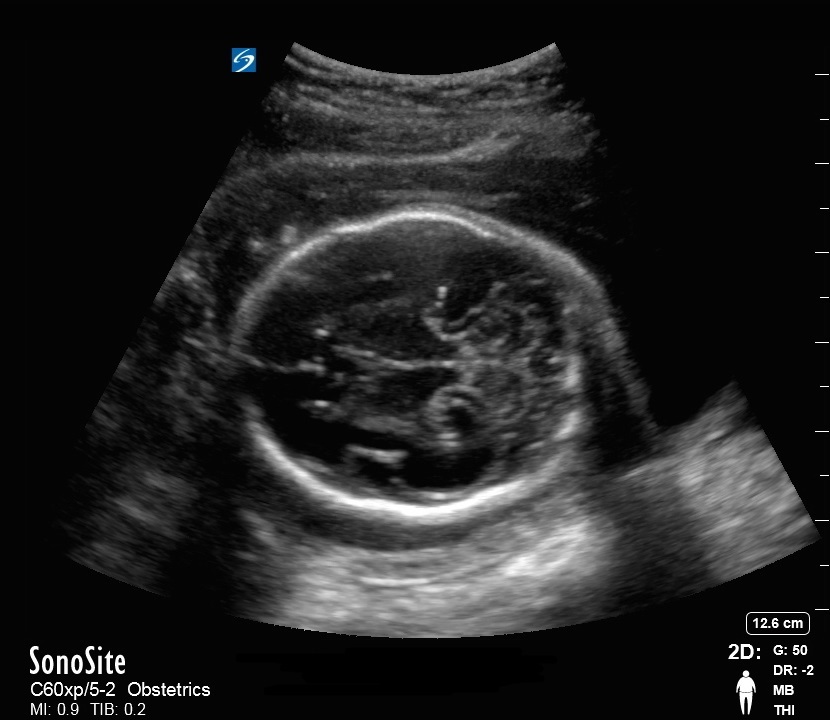

Bild: Becken, fetaler Kopf, biparietaler Durchmesser (BPD)